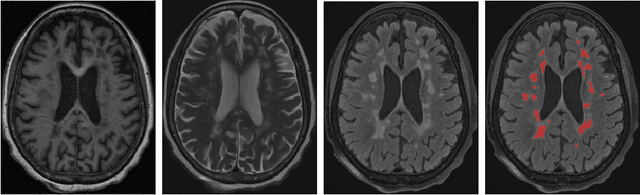

Abstract:Multiple sclerosis (MS) lesions occupy a small fraction of the brain volume, and are heterogeneous with regards to shape, size and locations, which poses a great challenge for training deep learning based segmentation models. We proposed a new geometric loss formula to address the data imbalance and exploit the geometric property of MS lesions. We showed that traditional region-based and boundary-aware loss functions can be associated with the formula. We further develop and instantiate two loss functions containing first- and second-order geometric information of lesion regions to enforce regularization on optimizing deep segmentation models. Experimental results on two MS lesion datasets with different scales, acquisition protocols and resolutions demonstrated the superiority of our proposed methods compared to other state-of-the-art methods.

Abstract:Recently, 3D medical image reconstruction (MIR) and segmentation (MIS) based on deep neural networks have been developed with promising results, and attention mechanism has been further designed to capture global contextual information for performance enhancement. However, the large size of 3D volume images poses a great computational challenge to traditional attention methods. In this paper, we propose a folded attention (FA) approach to improve the computational efficiency of traditional attention methods on 3D medical images. The main idea is that we apply tensor folding and unfolding operations with four permutations to build four small sub-affinity matrices to approximate the original affinity matrix. Through four consecutive sub-attention modules of FA, each element in the feature tensor can aggregate spatial-channel information from all other elements. Compared to traditional attention methods, with moderate improvement of accuracy, FA can substantially reduce the computational complexity and GPU memory consumption. We demonstrate the superiority of our method on two challenging tasks for 3D MIR and MIS, which are quantitative susceptibility mapping and multiple sclerosis lesion segmentation.

Abstract:Brain lesion volume measured on T2 weighted MRI images is a clinically important disease marker in multiple sclerosis (MS). Manual delineation of MS lesions is a time-consuming and highly operator-dependent task, which is influenced by lesion size, shape and conspicuity. Recently, automated lesion segmentation algorithms based on deep neural networks have been developed with promising results. In this paper, we propose a novel recurrent slice-wise attention network (RSANet), which models 3D MRI images as sequences of slices and captures long-range dependencies through a recurrent manner to utilize contextual information of MS lesions. Experiments on a dataset with 43 patients show that the proposed method outperforms the state-of-the-art approaches. Our implementation is available online at https://github.com/tinymilky/RSANet.